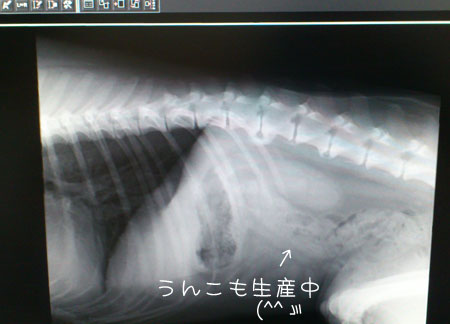

とりあえずレントゲンだけでも撮ってもらうことに。

それが、これ↓

絶食中なので、胃は、小さく縮、異物はない模様。

しかし、草やビニルのようは硬くない物はレントゲンには映らないらしい。

草やビニルなどは、胃の中で丸まって塊り、胃の出口をふさぐ事もあるので・・・

だから、要観察。

これが、↑ 横からの画像。

胃が塞がったり、活動していない場合、う●こが作られない。

しかし、胃の先の小腸、大腸、共に、しっかりとう●こが詰まっている。 < 食い過ぎ (^^ゞ

なので、完全に詰まっている事はないので、これまた要観察でO.K.との事。